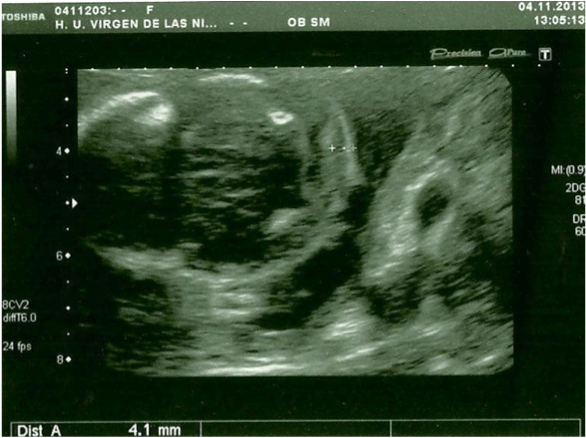

In the 20th week, a routine ultrasound, performed with an abdominal probe and ultrasound machine Toshiba Xsario X6, revealed a live fetus with biometry according to symmetric growth restriction (3rd centile for the gestational age) and estimated fetal weight, by Hadlock algorythm, of 201 grams. The ultrasound evaluation also showed a hypoplastic nasal bone (1.9mm) (Figure 1) without nuchal edema collapsed stomach and a single umbilical artery (Figure 2). Tricuspid regurgitation persisted and the fetal heart ultrasound was once again normal (Figure 3). Because of the risk of a genetic condition in the fetus, an amniotic fluid study was offered to the patient, and amniocentesis was carried out.

Figure 2: Axial prenatal ultrasonogram of a fetal head reveal normal nuchal

translucency (abdominal probe, Toshiba Xsario X6).